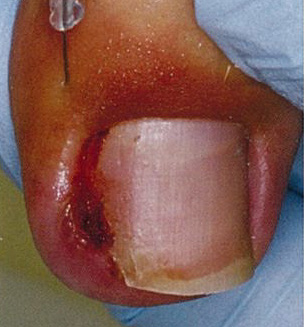

爪甲の側縁が皮膚に刺入して炎症をきたした状態、足の母趾で認められることが多いです。陥入爪では炎症や感染で強い痛みを伴います。

重症や難治性の方が対象です。皮膚に食い込んでいる爪甲側縁を必要最小限に切除し、刺さった状態を解除してあげることが大事です。局所麻酔を併用し、爪甲側縁を楔状に切除し、肉芽形成を伴う場合には肉芽も切除してしまいます。局所麻酔の痛みと出血がありますが、治療後は悩みの種であった痛みは数日内で治まり、皮膚の炎症は速やかに収束に向かいます。この方法では基本的に爪母が温存されることから、後遺症を残す可能性はほとんどありません。

①肉芽を伴った陥入爪